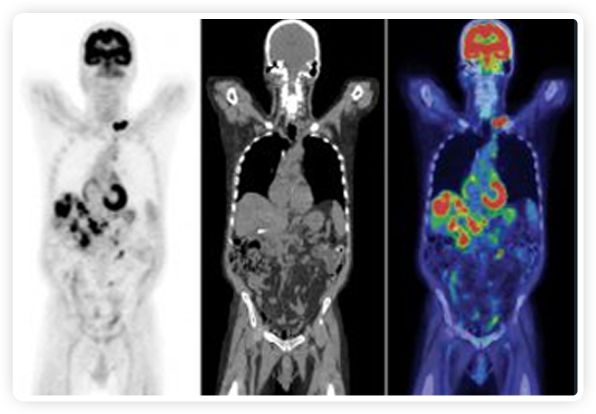

提起放療設(shè)備的引導(dǎo)系統(tǒng),大家通常會想到結(jié)構(gòu)性成像的CT或核磁。但你有沒有想過用功能性成像來引導(dǎo)放療呢?美國的一家醫(yī)療器械公司從2011年就致力于研究開發(fā)用PET提供生物學(xué)指導(dǎo)放射治療的設(shè)備BgRT。BgRT能實時利用癌癥的生物學(xué)特征作為信號指導(dǎo)治療全身腫瘤。

正電子發(fā)射斷層掃描(PET)是癌癥檢測中已建立的成像標(biāo)準(zhǔn),與其他成像方式相比,PET能提供高靈敏度和特異性的圖像。

到目前為止,放射腫瘤學(xué)中(使用的圖像主要是結(jié)構(gòu)性的,而PET圖像可以提供生物學(xué)信息。通過使用注射示蹤劑,例如18-FDG,PET可以描繪腫瘤的代謝活性,使其“點亮”。(FDG是用于可視化癌癥代謝的最廣泛使用的示蹤劑。與正常組織相比,腫瘤細(xì)胞保留更高水平的FDG。)不同的PET示蹤劑可以識別腫瘤的不同生物學(xué)特征,例如特定生物標(biāo)志物抗原(例如,PSMA)或甚至探測免疫系統(tǒng)本身(例如,PDL1表達(dá)或活化的T細(xì)胞)。

PET+放療共同治療

RefleXion將PET成像與立體定向放射治療相結(jié)合。在注射示蹤劑后,RefleXion的技術(shù)基于示蹤劑信號實時地在一個或多個目標(biāo)上引導(dǎo)治療性X射線。使用這種專有方法,RefleXion的平臺有可能比現(xiàn)有系統(tǒng)向癌癥病變提供更高劑量的輻射,并改善周圍健康組織的保護(hù)。